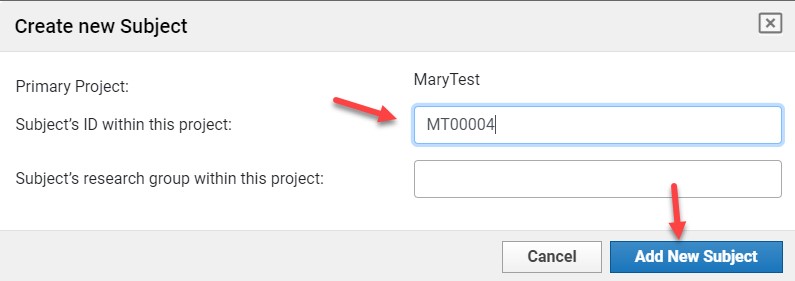

Start Upload

- Click Upload Files.

- Select the destination Project.

Only projects you have access to will appear.

- Click Browse and select the directory containing your image files.

- If prompted with anonymization options, select the file and click Upload.